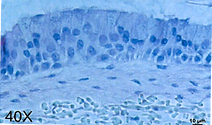

Airway Model

H&E-stained cross section of full-thickness human bronchial epithelial model produced on Bio-Spun™ PET Scaffold. The scaffold is populated with pulmonary fibroblasts which produce a fully human derived subepithelial matrix component. The fully developed pseudostratified mucociliary epithelium contains basal, goblet and ciliated cells with functional tight junctions.